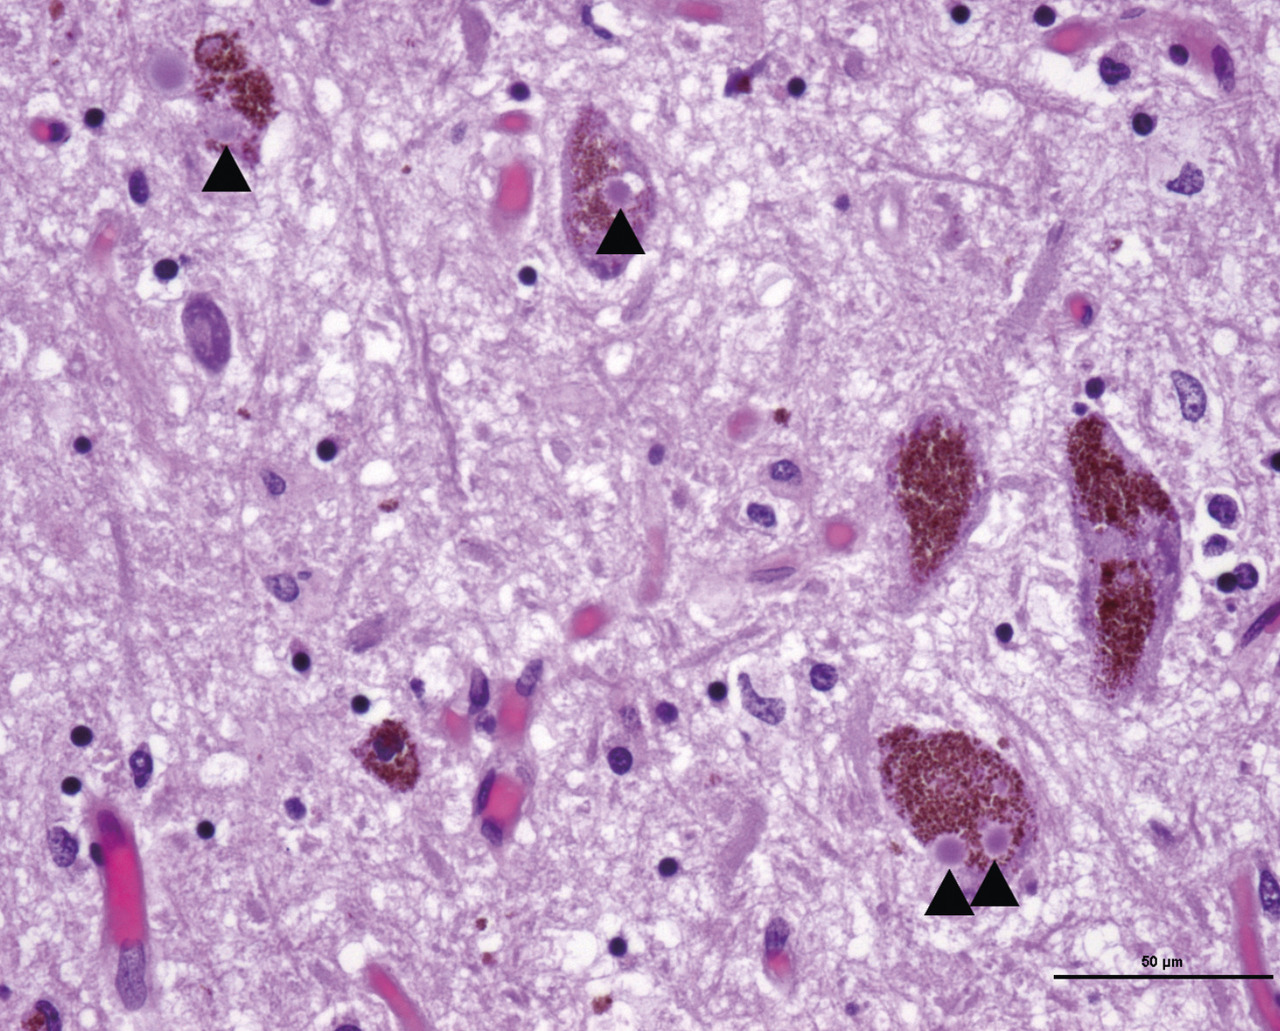

La lésion neuropathologique caractéristique est le corps de Lewy, inclusion éosinophile intraneuronale retrouvée dans les régions affectées par le processus dégénératif (fig. 1).

Dans la démence à corps de Lewy (fig. 1), la symptomatologie parkinsonienne s’associe précocement à une démence avec hallucinations et troubles fluctuants de la vigilance.